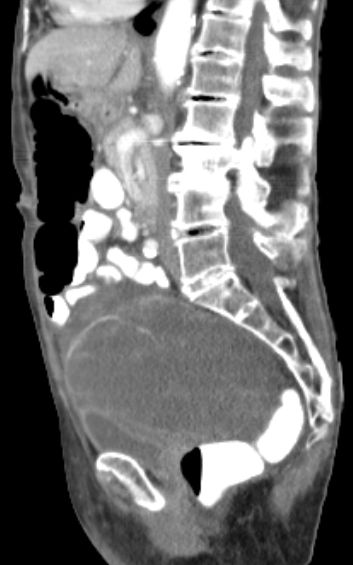

91-jährige Frau 2 Jahre nach OP einer muzinösen Neoplasie der Appendix. Jetzt Rezidiv.![]() |

![]() |